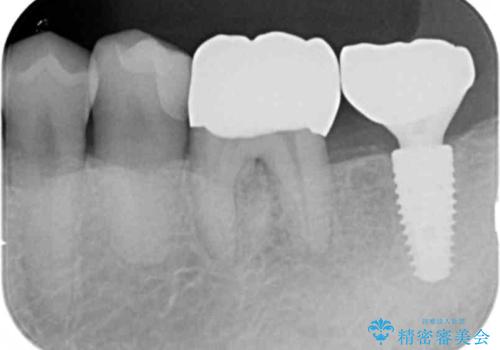

・重度虫歯による残根状態・欠損歯→インプラント補綴

・対合歯の欠損による歯の挺出→マイクロインプラントを用いた小矯正を行うことで咬合平面を是正